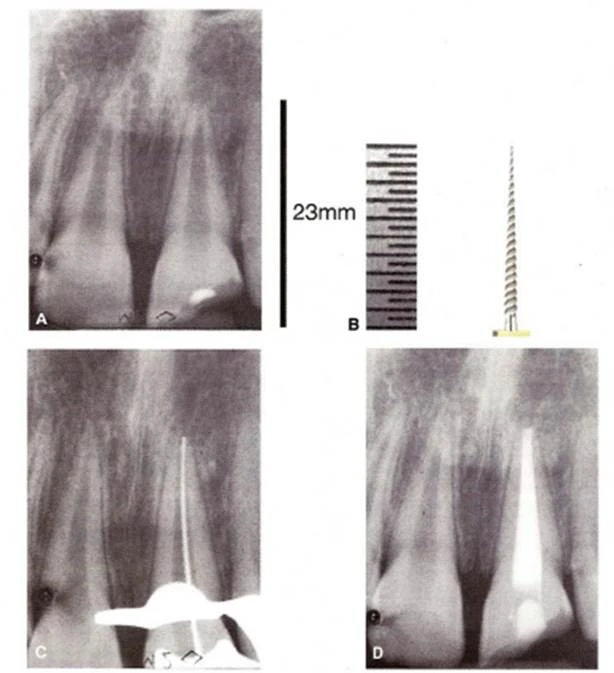

– Phương pháp xác định chiều dài làm việc bằng X-quang theo mô tả của Ingle:

+ Ước lượng chiều dài làm việc bằng cách đo trên một phim gốc răng chụp đúng đầu tiên

+ Đặt một cây trâm size 15 hoặc lớn hơn với chiều dài làm việc đã ước lượng ở trên và chụp một phim X-quang thứ hai.

+ Nếu đầu của cây trâm nằm trong 1mm xung quanh vị trí lý tưởng thì chiều dài nói trên có thể chấp nhận được và được xem là chiều dài của răng.

+ Nếu như đầu trâm chênh lệch 2mm hoặc hơn thì cần đặt lại trâm và chụp lại một phim khác để xác định lại chiều dài làm việc